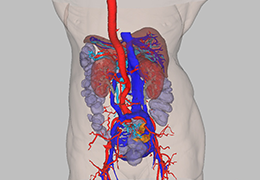

ANYTHINK 经导管主动脉瓣膜置换术分析系统